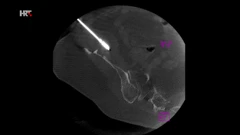

- Osmislio se način kako se precizno, pod kontrolom najčešće CT-a ili ultrazvuka, može iglicom ući u tumor. To može biti u različitim organima – bubregu, jetri, u kostima, čak i u plućima. Nakon što se ta iglica precizno pozicionira u tumor, toplinskom se energijom, laički rečeno - tumor sprži, uništi ga se. Ono što je važno, on ostaje unutra međutim ostaje kao mrtvo tkivo koje više ne predstavlja opasnost, kaže Luka Novosel, spec. radiologije iz KBC-a 'Sestre milosrdnice'.

Primjena ovakvih inovativnih metoda, osim edukacije liječnika, zahtijeva i korištenje suvremenih medicinskih uređaja i alata. Postupak se provodi iglom koja na vrhu, u zadnjih 2 cm - stvara različite vrste energije. U zadnje vrijeme koristimo mikrovalnu energiju kojom se potiče molekule vode u tumoru da se kreću, objašnjava Novosel. Tim trenjem stvara se toplina koja doseže i do 100 stupnjeva Celzijevih. Ona uništava tkivo u krugu od 3-5 cm.

Terapija kroničnih bolnih stanja kralježnice

- Zahvat se može korisititi i kokd kroničnih stanja kralježnice. Konkretno, radi se o zahvatu vertebralne ablacije kojega su tek prije par godina u Americi počeli upotrebljavati, a kod nas je nedavno uveden. Radi se u slučajevima gdje nema protruzije diska s pritiskom na živac, nego kronične upale i degeneracije diska koji onda uzrokuje i upalne promjene priležeće kosti u kralješcima. Takva su se stanja rješavala dosta invazivnim operacijama s jako teškim oporavkom. Tako da je ovo zaista inovativna i revolucionarna metoda, objašnjava Luka Novosel.